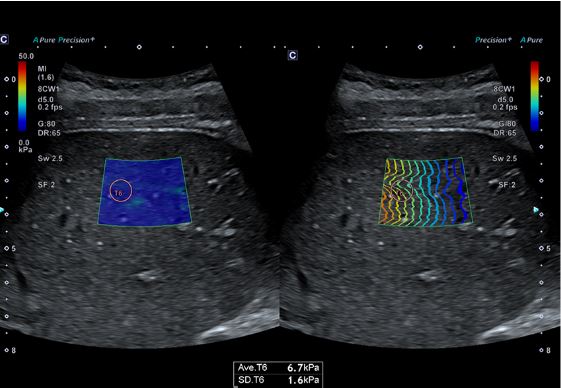

Еластографія зсувної хвилі (SWE) візуалізує швидкість зсувної хвилі та еластичність тканини для аналізу фіброзу печінки.